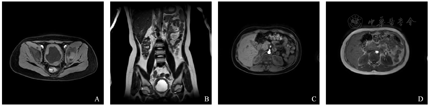

出院后规律减药,院外服药过程中每2周门诊复诊,复查血常规共6次,外周血镜检均未见嗜酸性粒细胞增多。2022年1月11日泼尼松减至5 mg×1/d。2022年1月18日因夜尿增多再次入院,查血常规:白细胞计数22.14×109/L,嗜酸性粒细胞百分比49.3%,嗜酸性粒细胞计数10.91×109/L。心脏超声提示:心包积液(微量)。胸腹超声未探及胸水、腹水。心脏超声示:心内结构未见明显异常;左室收缩及收缩功能正常;彩色血流未见明显异常。腹部超声示:肝、胆、胰、脾、双肾未见明显异常。胸部CT与前片(图1)对照:左肺上叶局限性肺不张较前复张;双肺多发索条较前减少;双侧胸腔积液、心包积液较前吸收;肺动脉增粗,主动脉弓管腔略细;食管壁弥漫性增厚(图4)。

A:左肺上叶局限性肺不张较前复张;B:双肺多发索条较前减少;C:双侧胸腔积液、心包积液较前吸收;D:肺动脉增粗,主动脉弓管腔略细;食管壁弥漫性增厚。

泌尿系MRI+MRU与前片(图2)对照:膀胱壁弥漫性不均匀增厚较前略明显;腹盆腔大量积液较前吸收;肠系膜根部、腹膜后、双侧腹股沟及髂血管旁淋巴结部分较前缩小(图5)。上调泼尼松至25 mg×2次/d,住院治疗4 d,患儿再无夜尿增多,复查血常规:白细胞计数17.58×109/L,嗜酸性粒细胞百分比7.7%,嗜酸性粒细胞计数1.35×109/L,遂出院。出院后予以口服泼尼松25 mg/早、20 mg/晚。出院后未再出现不适,规律门诊随诊及减药,每2周复查血常规均未见嗜酸性粒细胞增多,2022年3月6日停用泼尼松。截止2022年9月5日,随访患儿未复发。

A:T1横断位示膀胱壁弥漫性不均匀增厚较前略明显,双侧腹股沟及髂血管旁肿大淋巴结较前缩小;B:T2冠状位示膀胱壁弥漫性不均匀增厚较前略明显,腹盆腔大量积液较前吸收;C:T1横断位示肠系膜根部、腹膜后肿大淋巴结较前缩小;D:T2横断位示腹腔肿大淋巴结较前缩小。